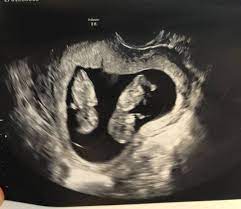

Pregnancy symptoms belly pictures. Its possible to be 11 weeks pregnant with twins and has no pregnancy. By 11 weeks in the twin pregnancy each of your twins will be about 16 inches long 41 mm from crown to rump.

Each baby is about the size of a fig or Brussels sprout. Your twins fingers and toes have formed and they may even be sucking their thumb by now. Get Weekly Twin Pregnancy Updates.

If you are having high hCG levels than normal in your pregnancy it could be an indication of twin or multiple pregnancy. An ultrasound is a definitive test to confirm a twin or multiple pregnancy. Having hCG level in line with the normal range be it single or multiple pregnancy does indicate good progress of the fetus during the initial weeks.